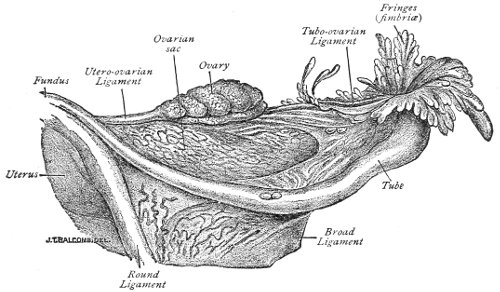

The origin of vaginal cysts has been much disputed. It is probable that they arise from the remains of the Wolffian canal—the canal of Gärtner. In the embryo the transverse or longitudinal tubule of the parovarium extends to the side of the uterus and thence down the side of the vagina to the urethral orifice. It persists in this condition in some of the lower animals—the sow and the cow—and may also persist as a closed tube in woman. In such cases it may become distended and form the vaginal cyst.